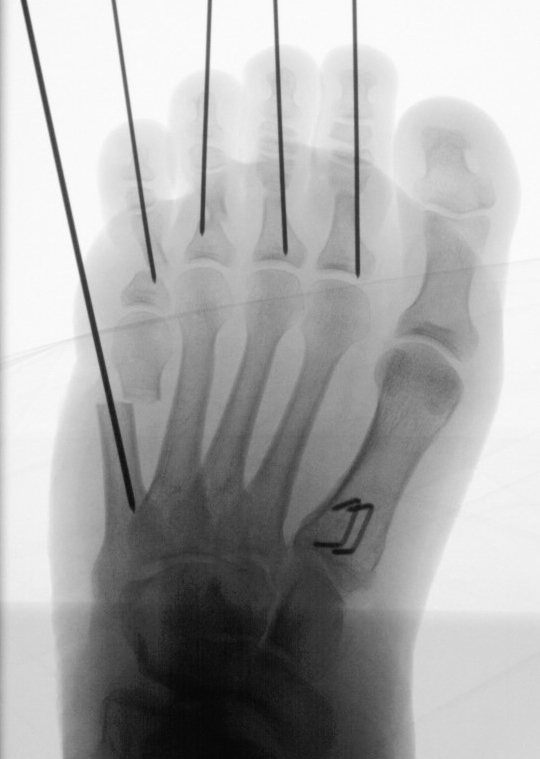

In der Regel bestehen aktive Wachstumsfugen bei Mädchen bis zum 12. und bei Jungen bis zum 14. Lebensjahr, mit Abweichungen von einem Jahr nach unten und nach oben. Präzise Informationen unter anderem darüber gibt das präoperative Röntgenbild (Abb. 2).

Abb. 2 a-c: offene Wachstumsfugen MT I Basis und Zehen (a), teilweise geöffnete Wachstumsfugen (b) und geschlossene Wachstumsfugen (c).

Zum Lesen der Bildbeschreibung und zur Vollansicht bitte die Bilder anklicken. Bilder: A. Helmers.